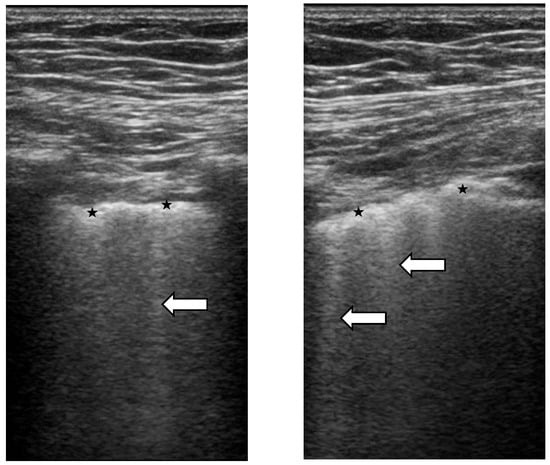

4. Lung Ultrasound

Lung Ultrasound in SSc-ILD: Qualitative Evaluation

- Warnecke, K.; Galanski, M.; Peters, E.; Hansen, J. Pneumothorax: Evaluation by ultrasound Preliminary results. J. Thorac. Imaging 1987, 2, 76–78. [Google Scholar] [CrossRef]

- Lichtenstein, D.; Mezière, G.; Biderman, P.; Gepner, A. The comet-tail artifact: An ultrasound sign ruling out pneumothorax. Intensive Care Med. 1999, 25, 383–388. [Google Scholar] [CrossRef] [PubMed]

- Singh, A.K.; Mayo, P.H.; Koenig, S.; Talwar, A.; Narasimhan, M. The Use of M-Mode Ultrasonography to Differentiate the Causes of B Lines. Chest 2018, 153, 689–696. [Google Scholar] [CrossRef] [PubMed]

- Soldati, G.; Demi, M.; Inchingolo, R.; Smargiassi, A.; Demi, L. On the Physical Basis of Pulmonary Sonographic Interstitial Syndrome. J. Ultrasound Med. 2016, 35, 2075–2086. [Google Scholar] [CrossRef]

- Buda, N.; Kosiak, W. Is a linear probe helpful in diagnosing diseases of pulmonary interstitial spaces? J. Ultrason. 2017, 17, 136–141. [Google Scholar] [CrossRef] [PubMed]

- Buda, N.; Skoczylas, A.; Demi, M.; Wojteczek, A.; Cylwik, J.; Soldati, G. Clinical Impact of Vertical Artifacts Changing with Frequency in Lung Ultrasound. Diagnostics 2021, 11, 401. [Google Scholar] [CrossRef] [PubMed]